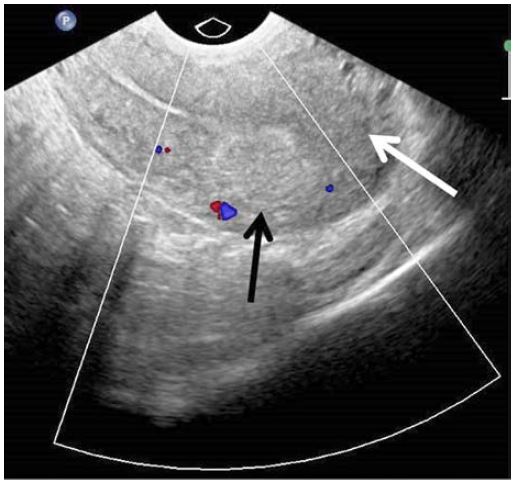

Following procedure the patient had a mild lower abdominal pain and no other symptoms or complications related to undergone embolisation. The patient was discharged from hospital the next day after embolisation. At one month follow-up visit transvaginal ultrasonography with colour Doppler showed resolution of AVM (Fig. 3) and the patient reported prolonged menstruation already lasting one week. At six month follow-up visit no recurrence of abnormal vaginal bleeding or vascular lesion within myometrium was found.